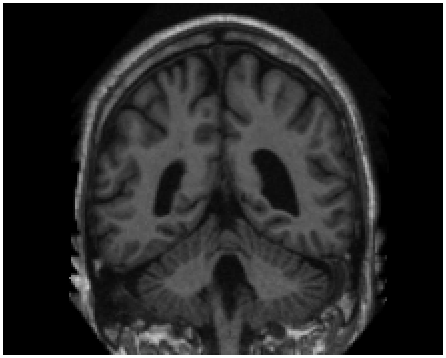

Refer to caption

(a)

(b)

(c)

Figure 4: Qualitative evaluation of reconstruction performance of our method on cardiac cine MRI (ACDC dataset). (a) Original cardiac MRI scan; (b) Its reconstruction and (c) Differences between original (minuend) and corresponding reconstructed (subtrahend) slice. Note that to reconstruct a slice xnsubscript𝑥𝑛x_{n} the mixing coefficient α𝛼\alpha in Equation 1 is set to zero. Blue corresponds to negative and red to positive differences. Image intensities are scaled to a [0,1]01[0,1] range. All difference images use the same color scale [1,1]11[-1,1].

Slice Reconstruction: Results for reconstructed and synthesized slices listed in Table I convey that the proposed approach achieved high reconstruction performance especially in terms of SSIM and PSNR. Figure 4 depicts qualitative results of reconstruction performance for the proposed method on cardiac MRI. The results show that the trained autoencoder can reconstruct high-quality images i.e. input slices. Nevertheless, difference image shown in Figure 4(c) depicts that some high spatial frequency details of the input slice are lacking in the reconstructed slice.